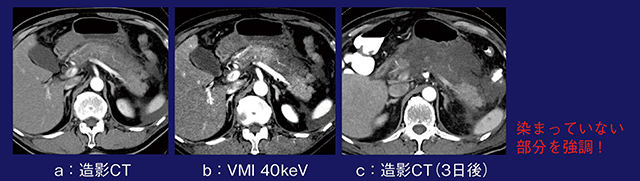

症例6は,71歳,男性,急性膵炎である。造影CT(図6 a)で認められた膵臓の造影不良域は,40keVの仮想単色X線画像でより明瞭となった(図6 b)。3日後の造影CT画像の所見とも一致しており(図6 c),仮想単色X線画像は濃染されていない部分を強調できるという点でも有用である。

図6 症例6:仮想単色X線画像による急性膵炎の評価